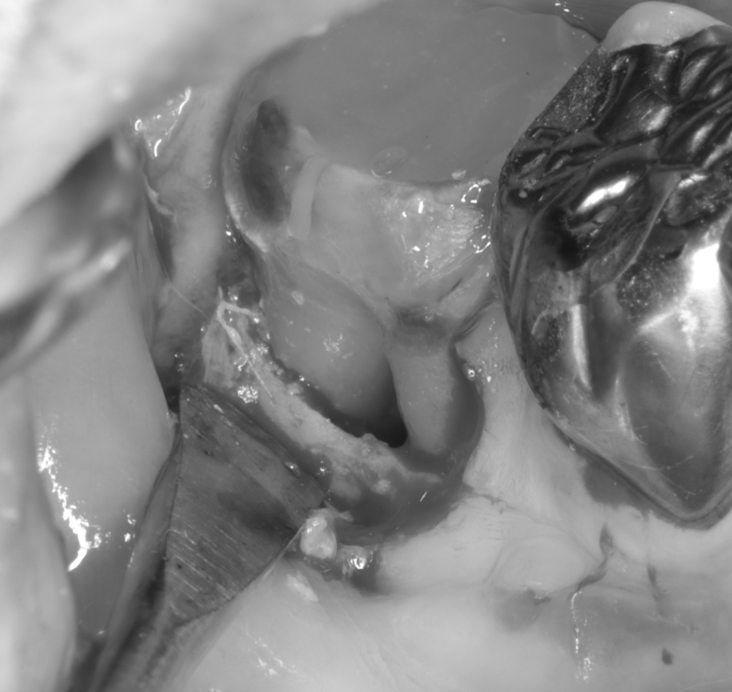

X線・CTにより、歯根分岐部に進行した骨吸収を確認。

骨支持の喪失が見られましたが、根面・感染範囲を精査し、再生療法の適応と判断しました。

治療中

| 治療内容 | 精密根管治療後、以下の流れで再生療法 ・感染組織と不良肉芽を除去 ・根面滑沢化(バイオフィルム除去) ・エムドゲイン®+骨補填材による再生誘導 ・縫合・閉鎖で再生環境を安定化 |